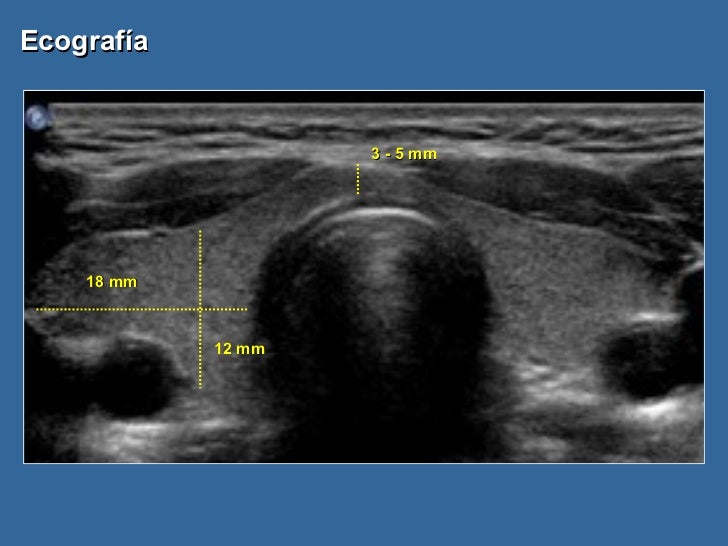

Узи tirads 3

Узи tirads 3 100 фотографий